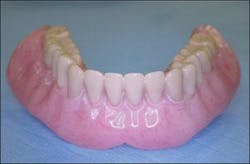

An interim immediate complete mandibular denture was fabricated prior to extraction of the mandibular teeth (Figure 2). The mandibular teeth were extracted and necessary alveoloplasty was performed (Figure 3).

Figure 3 - Mandibular ridges immediately post removal of mandibular teeth